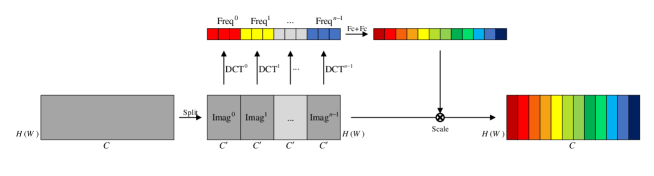

Traditional CNNs treat all channels in a feature map with the same importance, ignoring the importance differences. Therefore, the attention mechanism is adopted to make use of importance difference information by learning the different channel weights, i.e., effective channels have high weights and ineffective channels have small weights, which helps to train the model and enhance the results.

FCA Block (Qin, ) is a novel attention mechanism based on the squeeze and excitation block (SE Block) (Hu, ), as shown in Fig. 3. First, an feature map is squeezed into a vector. Then channel weights are extracted by two fully-connected layers, and channel weights multiply the original feature maps. A two-dimensional discrete cosine transform (DCT) is applied in FCA Blocks to squeeze the feature map, rather than global average pooling employed in SE Blocks, since this latter operation is equivalent to the lowest DCT frequency. Hence using only GAP leads to loss of other frequency components in the feature channel containing useful information. In the squeezing step, the feature map is divided evenly into parts (each size is ). The squeezing step can be represented as

where denotes the preset DCT template and denotes the corresponding frequency component. In this work, FCA Blocks are utilised after every residual blocks in the generator.